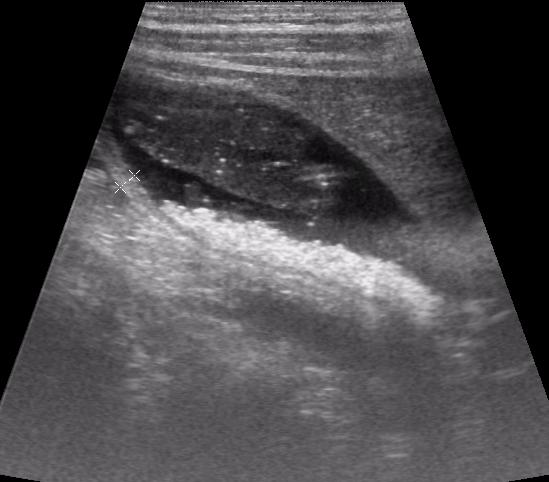

Большое спасибо за интересное сообщение, сегодня смотрела пациента, который лечится от пневмонии цефалоспоринами- псевдолитиаз.Я не поленилась, сходила в отделение и посмотрела амб.карту камней еще 1мес назад не было.

еще один пузырь (7 дней АБ)